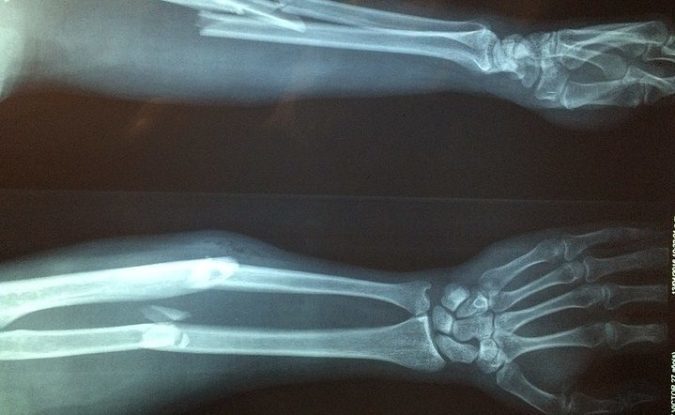

The bones of the arm are also some of the most commonly broken, particularly the humerus. The humerus is the large bone between the shoulder and elbow and a break often occurs as a result of a fall or a collision. It is the most common broken bone in children. The ulna, in the lower arm, is also a common bone to break.

There are many different types of breaks, including compound fractures, where the same bone breaks in a number of places, and a displaced fracture where the arm will look out of place and deformed. A closed fracture is where the skin hasn’t been broken and the arm looks more normal. A closed fracture is usually less serious and heals more easily.

The next most common break involves the wrist. The correct name for a wrist fracture is actually a ‘distal radius’ fracture or a ‘Colles’ fracture (after the 19th century surgeon who first described it). This is a common fracture in young people, as it is often sustained during activities such as skiing or skateboarding.

Staying in the wrist, sometimes a fracture can occur in the scaphoid bone without the sufferer realising, as there is usually very little swelling or deformity. A scaphoid fracture rarely heals without surgery however, so it is very important that a correct diagnosis is made.